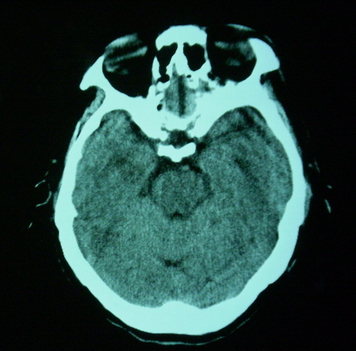

男,70岁,左侧肢体活动障碍口角向右侧歪斜2天,有高bp病史

pe:神情,能与之正常交流,吐字不清,180/90mmhg,双瞳孔无异常,左侧肢体肌力1级 b(+)

图中有个同心圆壮低密度影是ct伪影,见笑了。

1、右侧基底区及外囊区腔隙性脑梗塞。2、脑萎缩。

右基底节内囊前支区腔隙性脑梗塞,脑萎缩

基底区低密度影中含有伪影

右基底节区脑强隙 右基底节区低密度影密度太低 边界清 不会是2天的梗赛灶

2天左右的腔隙性脑梗死ct多难以发现 何况你的机器又差 很难显示 即使显示密度应该略低影

边缘模糊

支持腔梗。左内囊后肢亦有病灶